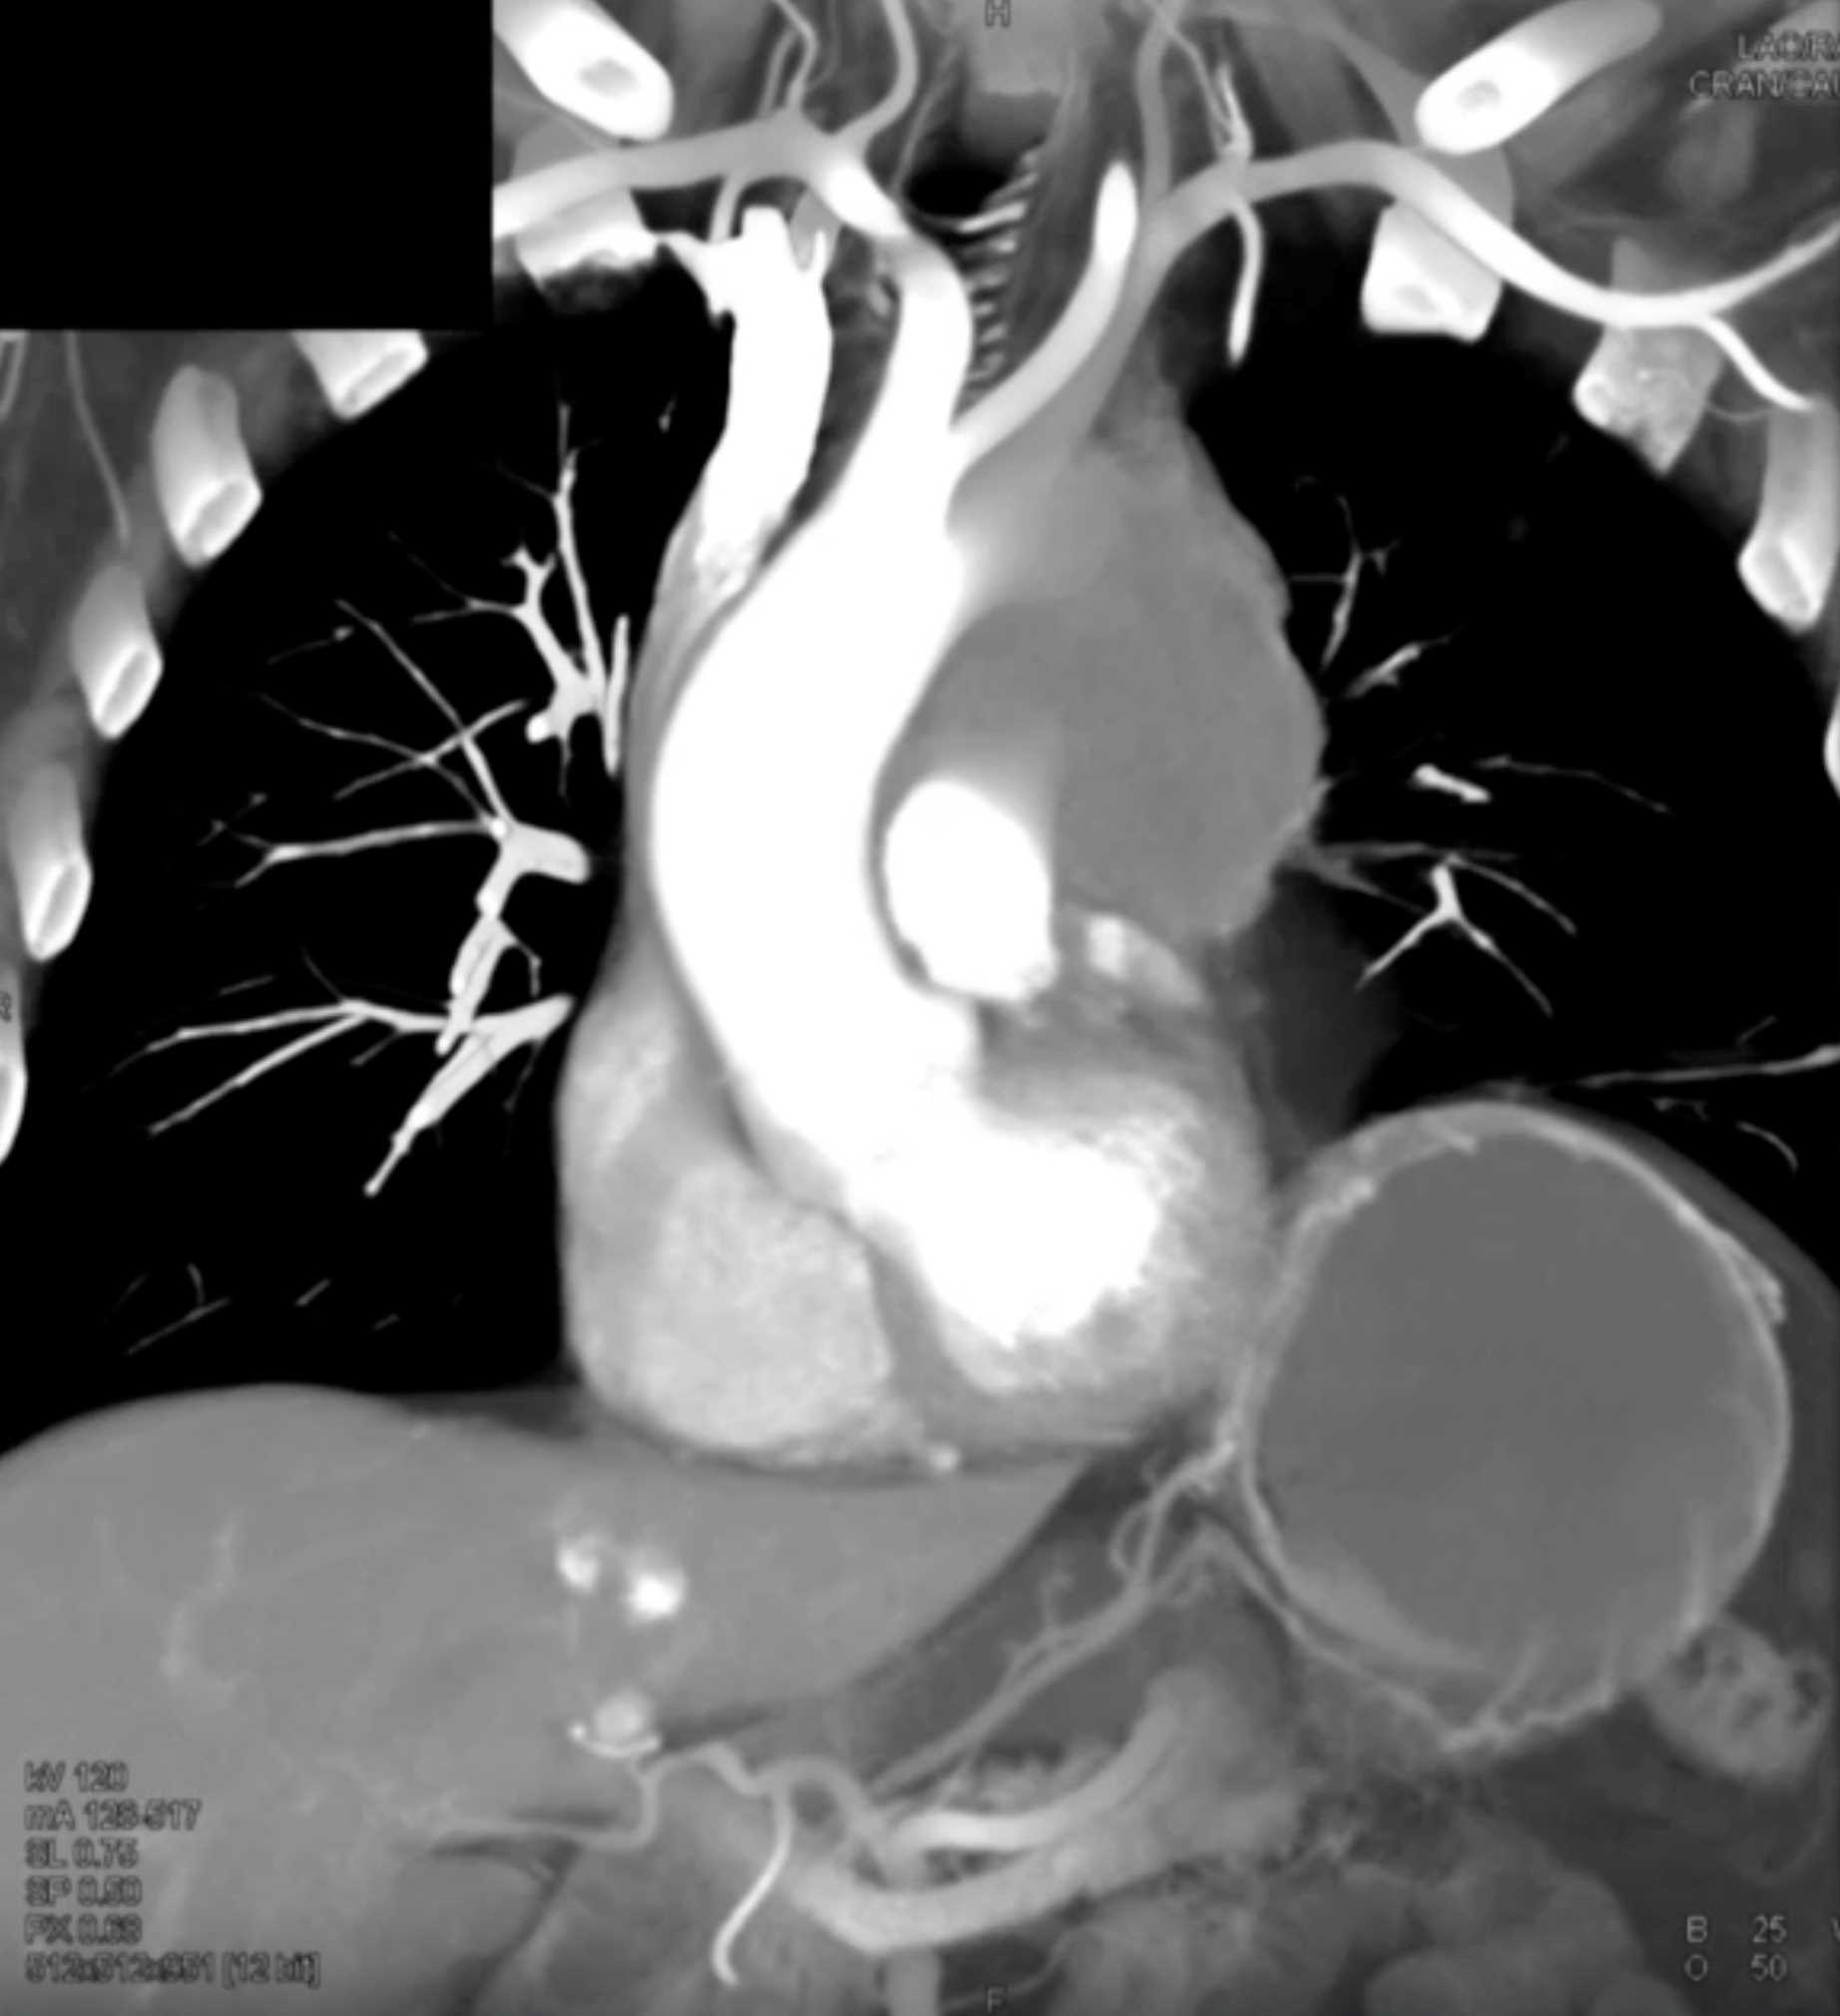

Thymic Carcinoma